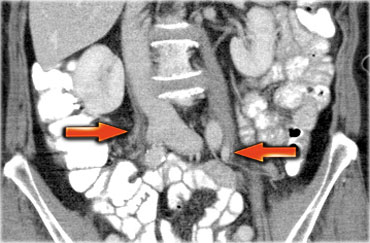

Một phương pháp hữu ích để xác định buồng trứng là theo dõi tĩnh mạch buồng trứng theo hướng đuôi.

Hãy cuộn qua các hình ảnh CT và theo dõi tĩnh mạch buồng trứng phải từ vị trí đổ vào tĩnh mạch chủ dưới, và tĩnh mạch buồng trứng trái từ vị trí đổ vào tĩnh mạch thận trái, cho đến khi xác định được buồng trứng.